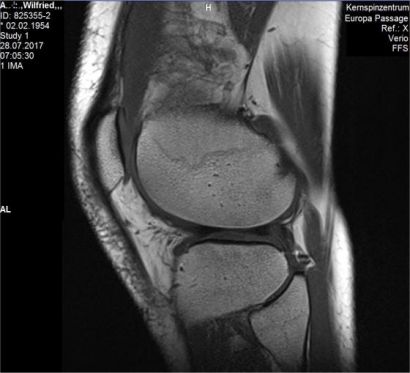

Des Orthopäden erste Vermutung, ich hätte mir einen Meniskusschaden zugelegt, erwiesen sich nur als halbe Wahrheit. Eine Magnetresonanztomographie (kurz MRT) zeigte es auf: Die Menisken hatten sich geradezu deformiert und zudem kam ein Knorpelschaden hinzu. Das war jetzt vor gut anderthalb Jahren. Die Arthrose des Kniegelenks, Gonarthrose genannt, gehört zu den häufigsten Abnutzungserscheinungen der Gelenke. Der fortschreitende Gelenkverschleiß führte dazu, dass der Knorpel im Kniegelenk zerstört wird.

MRT des rechten Kniegelenks